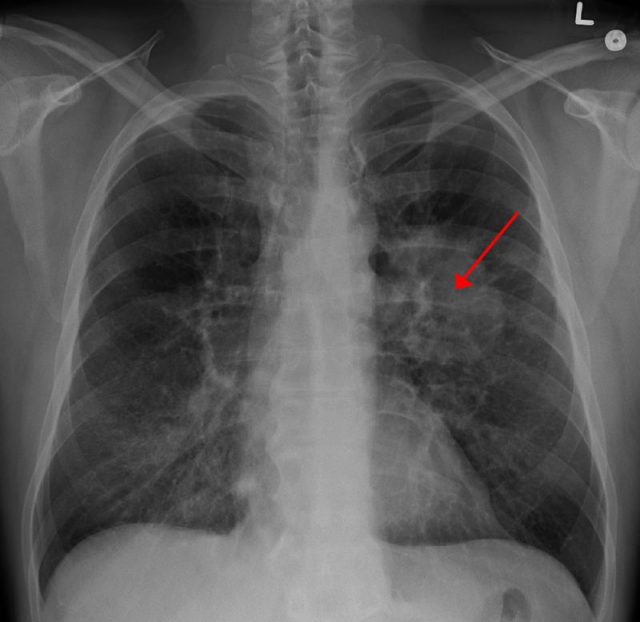

Rakovina plic

Rakovina je strašákem současnosti a můžeme-li věřit předpovědím odborníků, bude ještě hůř. Už nyní umírá na světě v důsledku této nemoci jeden člověk každých pět vteřin, celkem na ni ročně zemře 8 milionů lidí a u 14 milionů je každý rok nově diagnostikována.

U mužů výskyt mírně klesá, u žen roste (podle dat za rok 1977 až 2016 klesl roční výskyt onemocnění u mužů o 9,9 %, u žen vzrostl o 32,8 %).